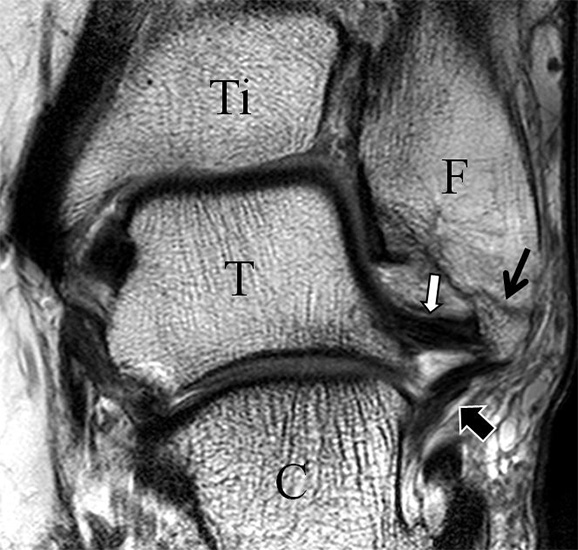

Man unterscheidet bei dem Ligamentum deltoideum eine tiefe Schicht (Pars tibiotalare posterior, Pars tibiotalare anterius) und eine oberflächliche Schicht (Pars tibionaviculare, Pars tibiocalcaneare, Pars tibiotalare posterius superficialis und Tibiospring-Ligament) 10. Hochauflösende Techniken lassen eine differenzierte Beurteilung aller Bandanteile zu. Sowohl rein ligamentäre als auch osteo-ligamentäre Ausrisse sind normalerweise gut zu erkennen. Die Pars tibiotalaris posterior ist multifaszikulär aufgebaut und sowohl axial als auch coronar (Abb. 19 a) gut bildgebend abzugrenzen. Die deutlich kleinere, nur inkonstant angelegte Pars tibiotalare anterior inseriert an einem kleinen Talustuberkel (Abb. 19 b). Ossäre Bandausrisse kommen hier gehäuft vor. Proximal verlaufen die Pars tibiocalcaneare und die Pars tibionaviculare gemeinsam (Abb. 19 c) nach kaudal und trennen sich dann in zum Calcaneus und zum Os naviculare ziehende Bündel auf. Ein besonderer Typ ligamentärer Verbindungen stellt das Tibiospring-Ligament dar. Es verbindet nicht wie für Ligamente typisch zwei Knochen miteinander, sondern es hat seinen ossären Ursprung an der Tibia und inseriert am Pfannenband (Ligamentum calcaneonaviculare plantare, im englischen Schrifttum Spring-Ligament genannt), also nicht ossär. Das Innenband ist mit 60% der Verletzungen am häufigsten betroffen. Isolierte Innenbandverletzungen sind jedoch selten. Sie treten gehäuft assoziiert mit Syndesmosenläsionen, Fibulafrakturen, Verletzungen des Muskulus tibialis posterior und des Pfannenbandes auf (H.-K. Beyer 2003). Entsprechend sollte auf diese Kollateralverletzungen bei der Beurteilung geachtet werden. Eine weitere Folge von Verletzungen des Ligamentum deltoideum ist die chronische Sprunggelenksinstabilität. Arthroskopisch weisen hier bis zu 40% der Patienten einen elongierten Verlauf des Ligamentum deltoideum auf. In diesem Patientenkollektiv besteht auch eine erhöhte chondrale Komorbidität mit arthroskopisch erkennbaren Knorpelschäden (98%) im Gegensatz zu der Patientengruppe (66% Knorpelschäden) mit reiner Außenbandinstabilität 11. Dies belegt die klinische Bedeutung von Innenbandverletzungen.